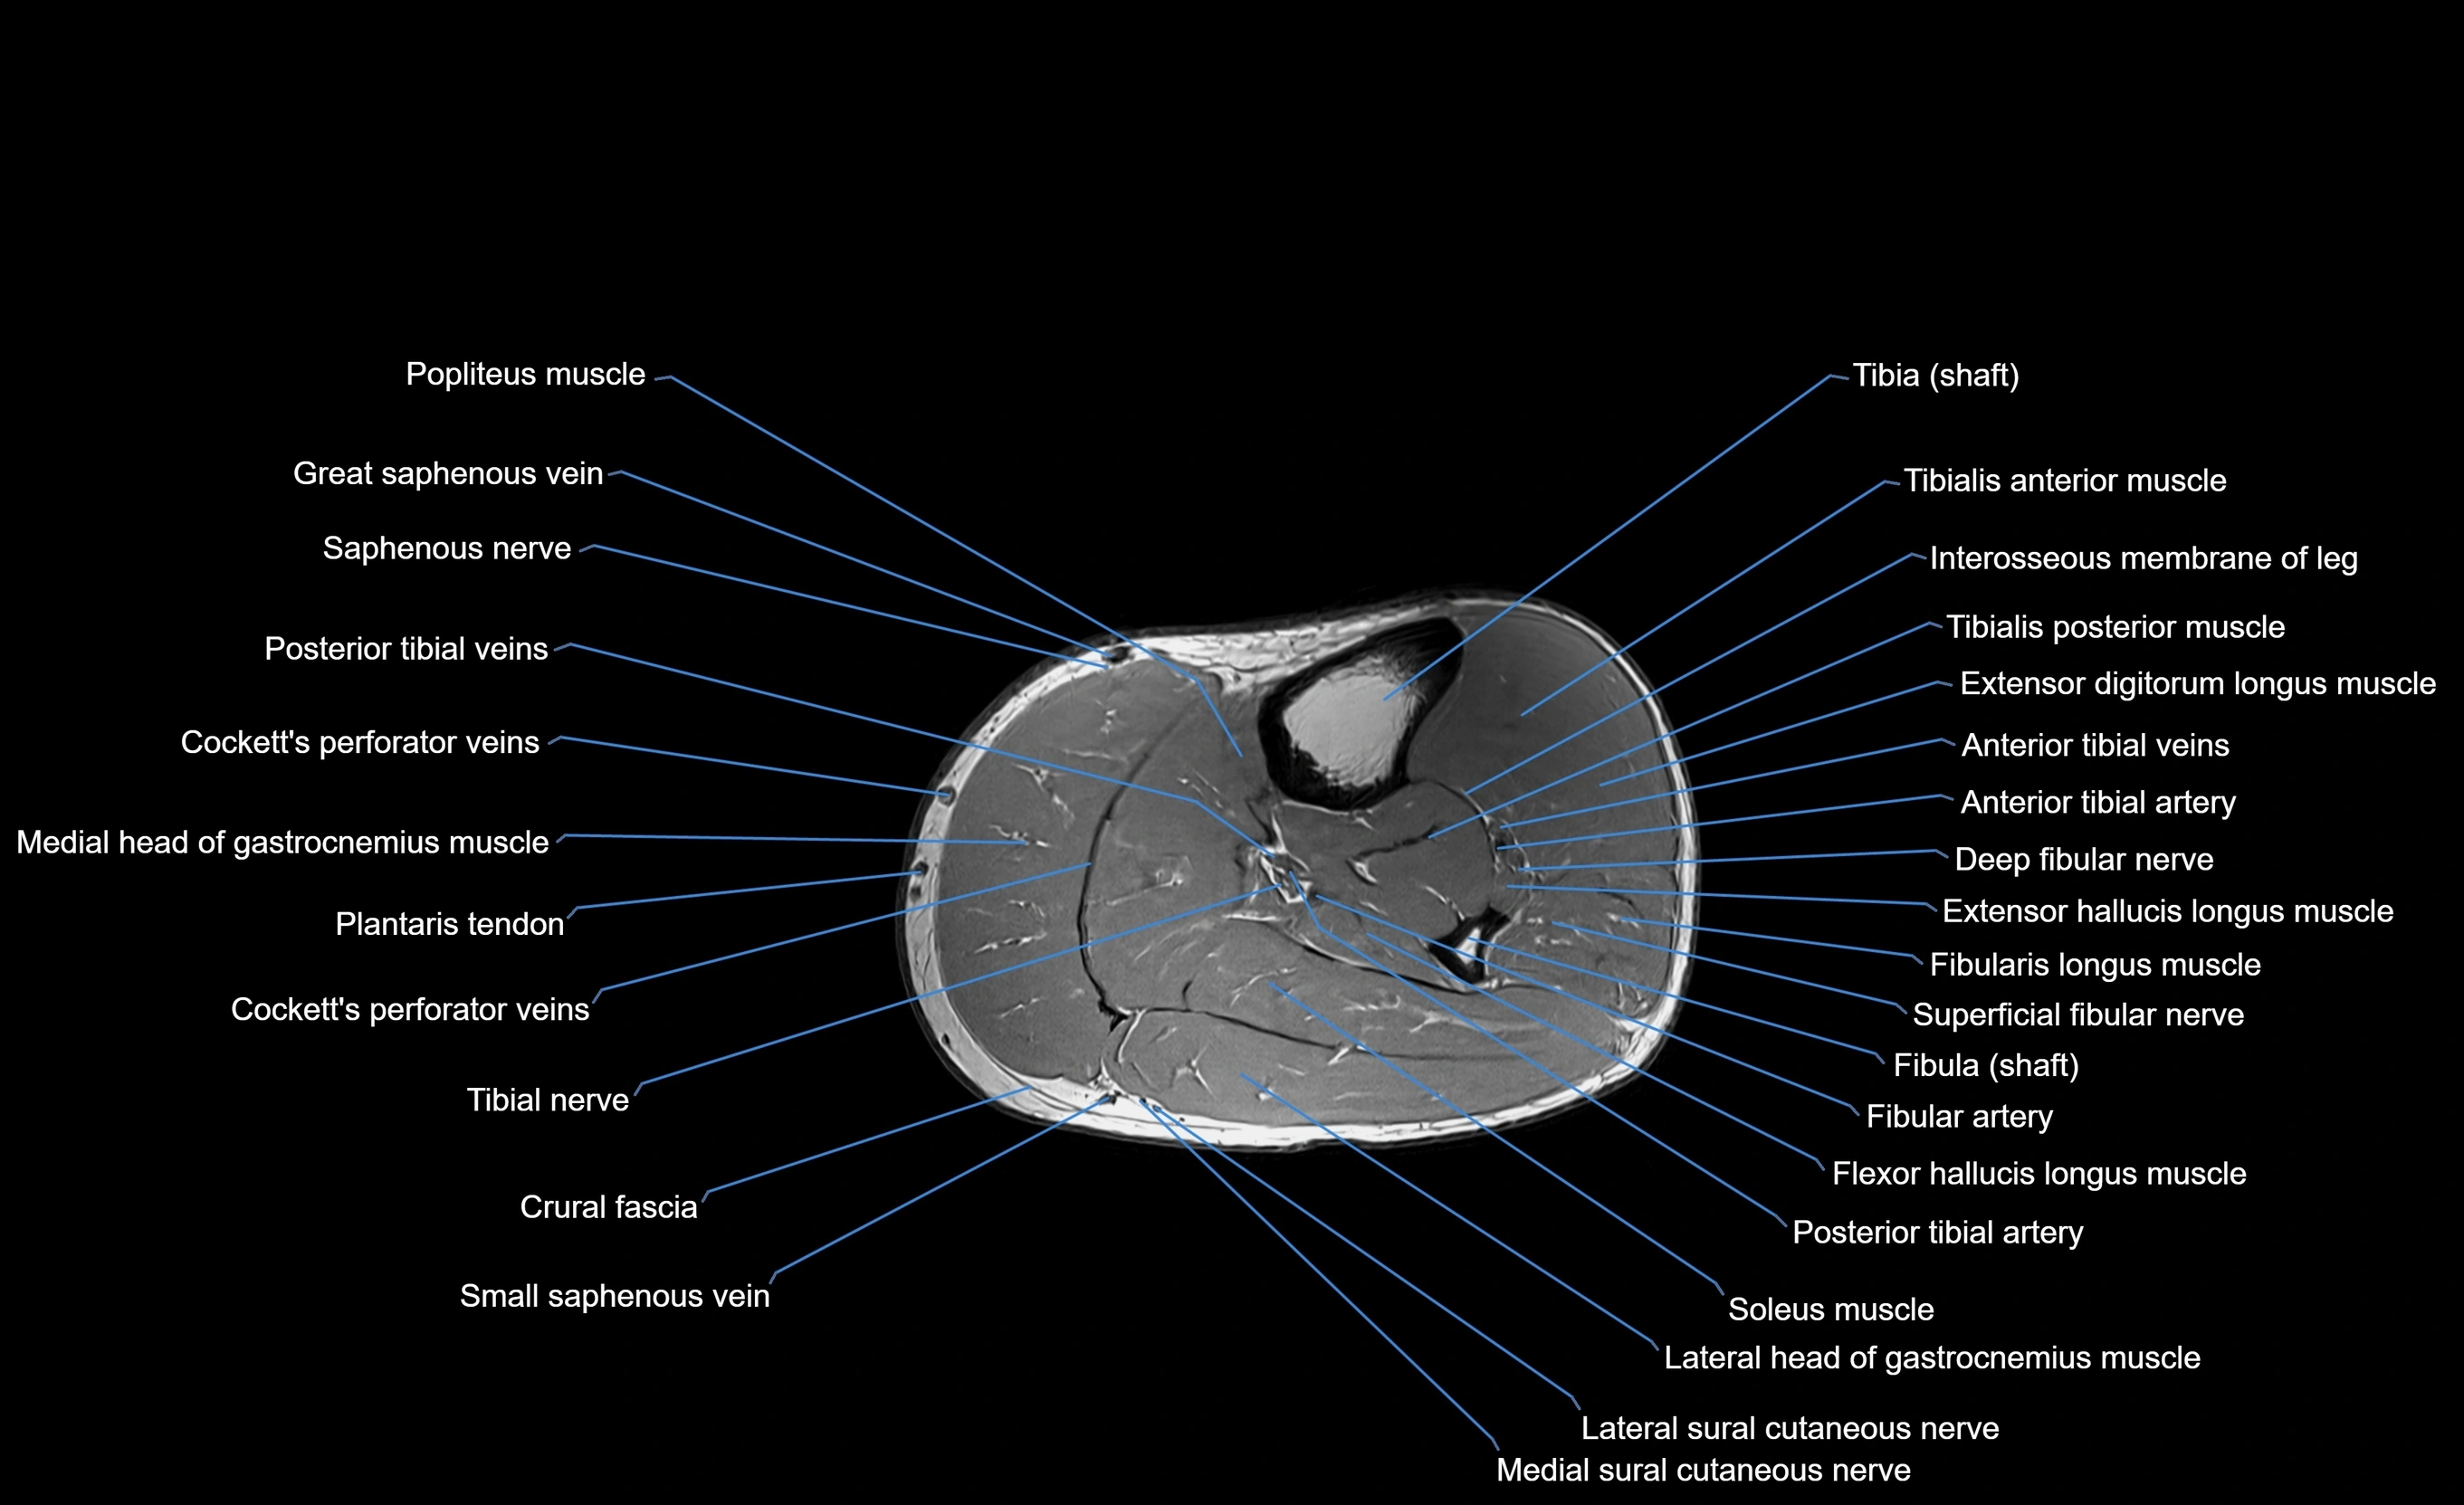

- Tibialis anterior muscle

- Tibialis posterior muscle

- Extensor digitorum longus muscle

- Fibularis longus muscle (peroneus longus muscle)

- Soleus muscle

- Lateral head of gastrocnemius muscle

- Medial head of gastrocnemius muscle

- Popliteus muscle

- Tibial nerve

- Posterior tibial artery

- Deep fibular nerve

- Superficial fibular nerve

- Fibular artery

- Flexor hallucis longus muscle

- Saphenous nerve

- Cockett’s perforator veins